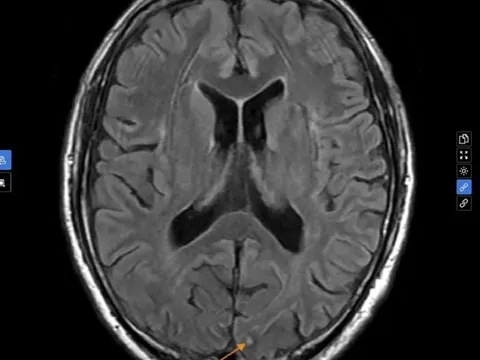

Nhìn mờ thoáng qua rồi tự hết cũng có thể là dấu hiệu đột quỵ nguy hiểm, vì sao?

Nam bệnh nhân 67 tuổi, quốc tịch Nhật Bản, bất ngờ xuất hiện tình trạng mắt nhìn mờ trong khoảng 30 phút, ít ai biết đây là dấu hiệu đột quỵ.